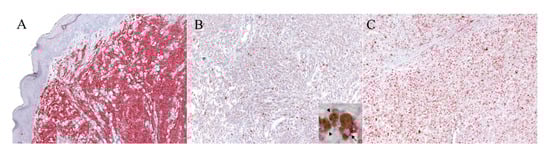

The slides were visualized at 40× magnification using a D-Sight scanning machine and the D-Sight Viewer software (A. Menarini Diagnostics). The KIT index was evaluated by counting the mean number of positive cells in 5 consecutive high-power fields (hpf; 0.237 mm2) within the areas with clear positive staining, starting from the mostly positive field. If no positive cells were found in 3 consecutive hpf, the process was repeated in another IHC-positive area. This method was designed similarly to that used for the establishment of the Ki67 index as described by Bergin and colleagues [], which was applied for the Ki67 index calculation. When more than one biopsy was present for each tumor (e.g., for margin evaluation), 5 hpf were selected for each specimen. Only areas with a cellular population representative of the tumor were selected, and areas affected by background, degeneration, scirrhous reaction, or necrosis were avoided. Neoplastic cells were considered positively KIT-labeled when they showed brightly red cytoplasmic and membrane staining, as exemplified in Figure 1A from the MCT control, and as described in the literature [].

Figure 1.

IHC for KIT and Ki67 with the RED labeling system. (A) Mast cell tumor (MCT). Example of the mast cell tumor used as the control tissue for the KIT immunolabeling, with a high density of positive cells (100× magnification). (B,C) Canine oral melanoma (COM). (B) Example of a neoplastic area selected for the evaluation of the KIT index, which was 6.6 (100× magnification): the positive cells are discernible and scattered throughout the field. The details of the positive neoplastic melanocytes (arrow) are provided with higher magnification in the inset; melanomacrophages are also present within the inset (arrowheads). (C) Example of a neoplastic area selected for the evaluation of the Ki67 index, which was 30 (100× magnification).

As expected, the anti-KIT antibody showed cytoplasmic and membranous labeling of neoplastic melanocytes with a bright multifocal positivity of a scarce to a moderate number of cells (Figure 1B). The positive cells were discernible and randomly distributed across the tumor tissue in the majority of samples; particular patterns of distribution were not noted. Only two samples (15.4%) did not show any staining for KIT expression.

The KIT index varied from 0.6 to 8.6 in positive samples, with a mean of 3.1 positive cells in 5 hpf. Positive staining for the anti-Ki67 antibody (Figure 1C) was obtained for all specimens and the Ki67 index was established as described []. The Ki67 index varied from 7.6 to 265, with a mean of 62.4 positive cells in 5 hpf. According to the Ki67 prognostic cut-off of 19.5, three samples were classified as having a good prognosis (G), and the remaining 11 as having a bad (B) prognosis. The results are summarized in Table 1. When samples were divided into two groups according to the KIT amplification status, no statistically significant differences were detected either for the KIT index (p = 0.56) or for the Ki67 index (p = 0.38). Similarly, no differences in terms of KIT and Ki67 expression were noted between males and females (p = 0.87 and p = 0.46, respectively), or according to the pigmentation level (p = 0.48 and p = 0.73, respectively). Finally, no correlation was found between the two indexes (r = 0.074, p = 0.81).